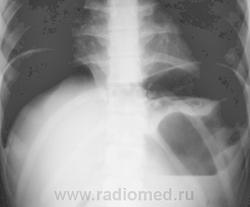

Да, на обзорге ОГК стенка свода желудка ровная, тонкая (париетография прям). А на РГ ОБП между газом слева и пузырем желудка какая-то тень, может кровь натекла?

А рана где? Может это внутристеночная гематома желудка (негомогенно смотрится). Однако же, коллеги, ну пофантазируйте: вот два снимка, на одном стенка свода линейная, на втором - нет. Что это (кроме занудного ответа "скиалогия":)

Газ в брюшной полости понятен.Не понято,что в желудке.

Вы об уровне жидкости, та, что в желудке?

Нет,там сверху что-то свисает,могу ошибаться.

Со слов оперировавшего хирурга, большое количество крови было в сальниковой сумке...